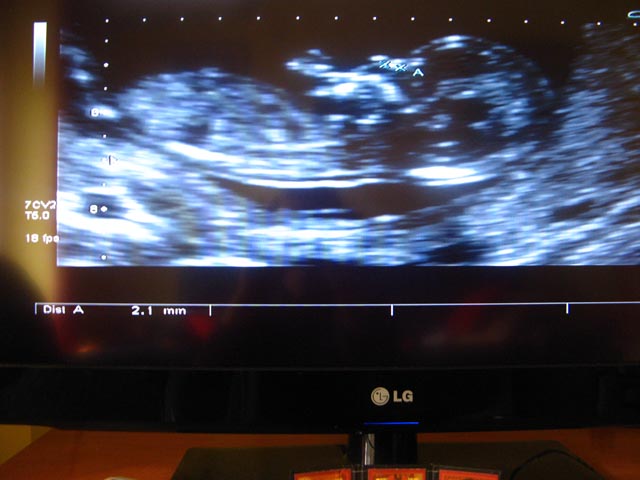

Sorry you´re worried ZB. The tech saw the nasal bone the second day right? so you don´t have to worry about that now.

How far along are you, maybe it was early and the nub will still rise (if it is flat now, I don´t know).